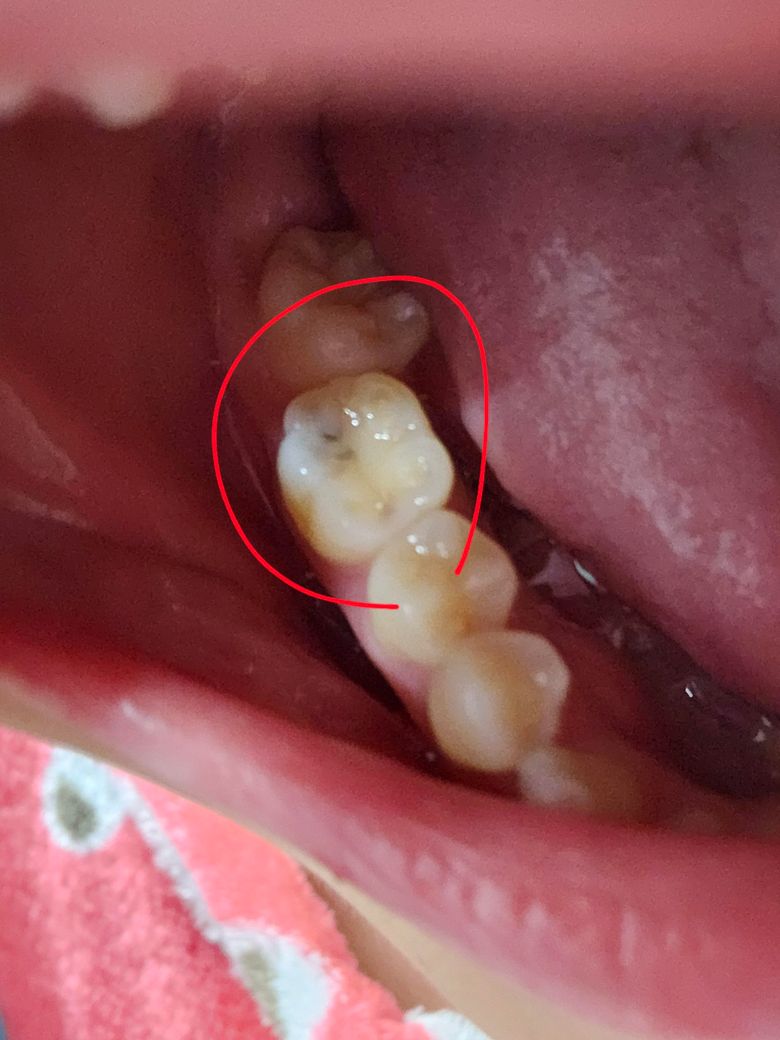

이거 충치인가요???????급해요ㅠㅠㅠㅜ

사진처럼 어금니가 저런데 이거 충치인가요? 아프거나 하진않아요. 어떻게하면 충치를 없앨수있나요? 이 잘닦으면 사라질까요?

불소치약쓰는게 도움될까요?

사진상으로는 명확한 충치가 있는 것으로 관찰됩니다. 치과를 빨리 가보시는 게 좋겠습니다.

충치인 것으로 보입니다. 저 정도 크기 충치는 치료해야 합니다. 하지 않으면 점점 진행됩니다. 잘 닦는다고 해결되지 않습니다.

사진으로 봐서 충치의 가능성이 있어 보입니다. 이미 생긴 충치는 없어지지는 않습니다. 치과가서 치료 필요여부에 대해 판단받아보시기 바랍니다.

사진으로 봤을 경우에는 작은 충치가 있는것으로 보입니다. 치과에서 간단하게 치료할수 있으니 정확한 확인을 위해서 치과에서 진료를 받아보세요.